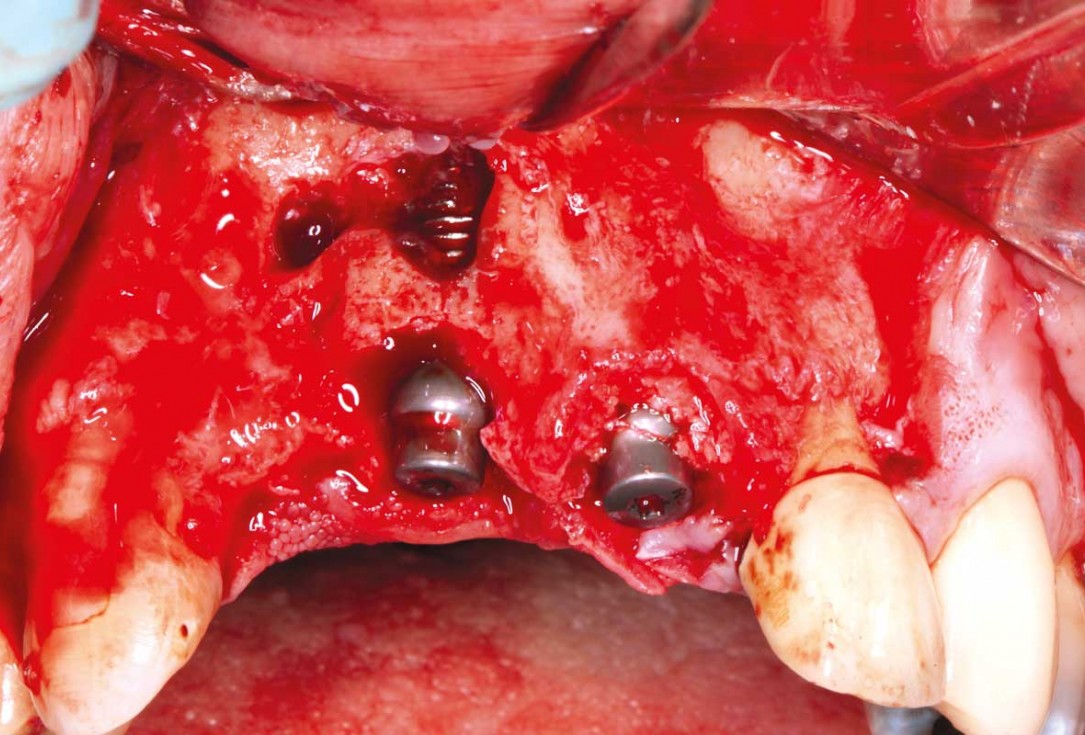

2/27 - Bone defect after raising the flap

GBR and soft tissue augmentation with cerabone® and mucoderm® - H. Maghaireh & V. Ivancheva